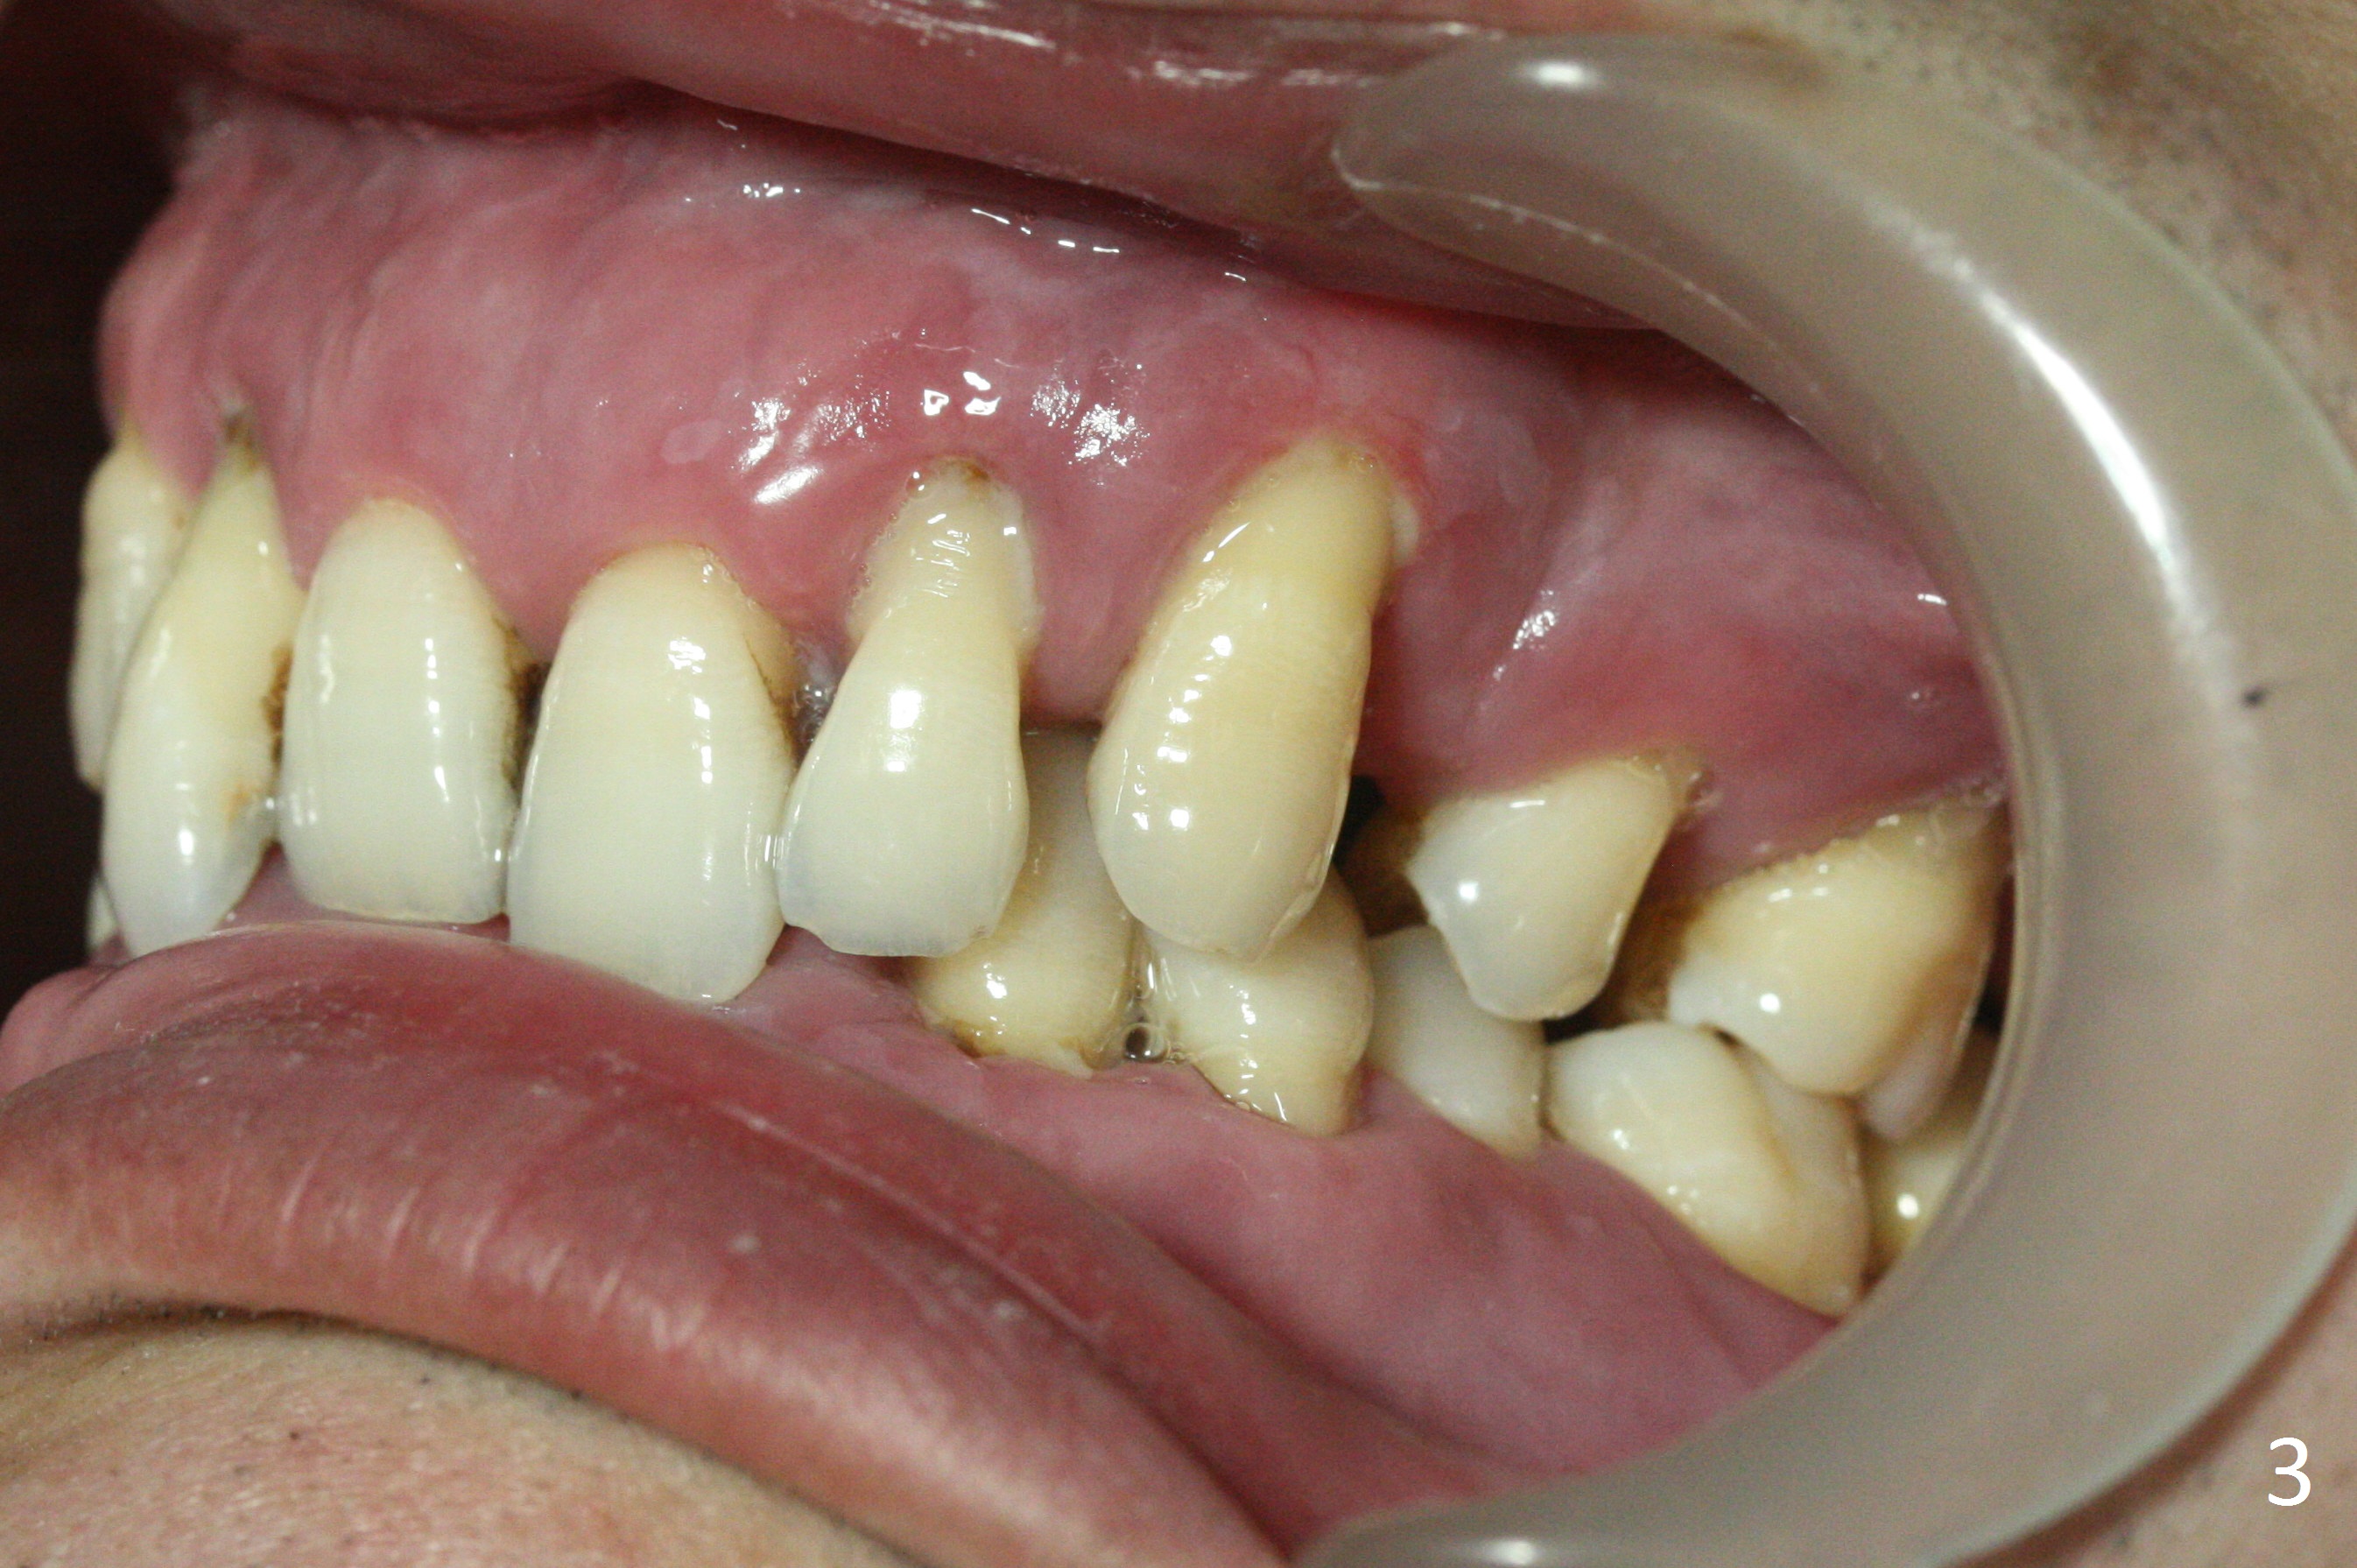

A 36-year-old man (ex-smoker) has advanced chronic periodontitis (Fig.1-5). His chief complaint is "I cannot chew on the right side now because of pain (Fig.1: #3 abscess <) and the bottom front teeth are loose (Fig.2,5: #23-26)". He has not masticated on the left side because of the mobile teeth. Due to finance, implants will be placed at #3,4 (Fig.12), 23 and 26 at the appointments of scaling & root planing.

Class II Division II malocclusion (Fig.2,6) will make it difficult to restore #23-26 implant-supported FPD. Although the teeth #7-10 may need to be replaced later (Fig.7,8), enameloplasty will be conducted for #7-10 (Fig.9 white area; Fig.12 black circles (gross reduction)) prior to #23-26 extraction and implant placement (Fig.10). To be flexible in restoration (angulation) and possible future hybrid denture, 2-piece narrow implants will be placed (3.0 or 3.3 mm) instead of 1-piece ones. In fact CBCT shows that the narrowest regular implant (3.8 mm) can be placed in the lower anterior region (Fig.13-15).